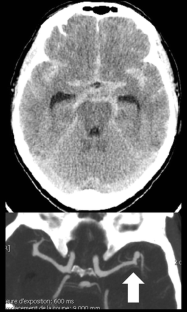

The utility of this method is illustrated in a case of a ruptured middle cerebral artery (MCA) aneurysm. Two temporary aneurysm clips were connected by a braided suture, thus forming a band with two points of attachment. The Sylvian fissure was opened in a standard fashion. Using one clip, the adventitia and arachnoid over the superficial Sylvian vein were grasped firmly enough to mobilize the superficial Sylvian vein. The distal clip was then attached to surrounding drapes, thus granting a direct view of the aneurysm in the depth of the fissure. Retraction with spatula was not necessary. Patency of the superficial Sylvian vein was demonstrated using idocyanine green angiography.

We present a simple method for minimally traumatic brain retraction using aneurysm clips attached to the adventitia of Sylvian veins and held back by sutures.

The use of clips attached to the adventitia of the superficial Sylvian may be of help in retracting the Sylvian fissure. By virtue of enlarging the field of view into the deep Sylvian fissure, it may be of help in performing retractorless aneurysm surgery.